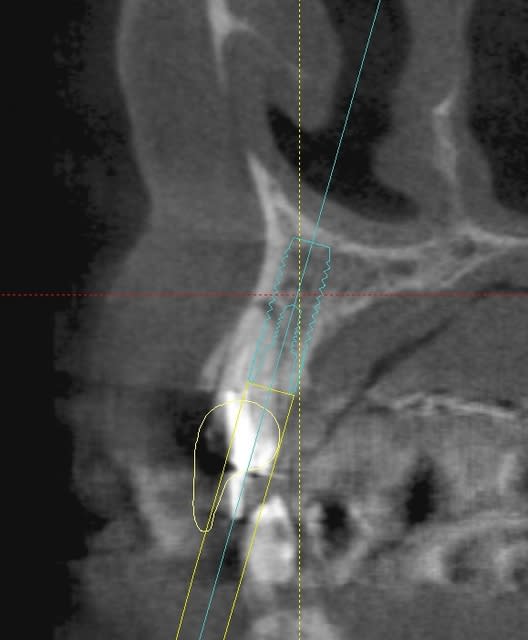

une petite étude de ton cas avec implants osseosped Astra :

12 : 3.5 x 11

13 : 3 x 11 (?)

14 : 3 x 11 (?)

15 : 3.5 x 11 (?)

16 : 4 x 11

17 : 4 x 11

je ne pratique pas donc pas de conseils sur ces implants.

techniquement:

extraction de 12 , curetage soigneux.

vue la qualité osseuse :

si D4 :

saignée à la lame n°15

si D3 :

avec un disque diamanté 10 x 0.3mm incision crestale de 12 à 16 ou 17

puis avec un disque de 20x0.3mm ou à la lame 15 approfondissement de la saignée

puis expansion en "douceur" (sans incision de décharge verticale, à priori car la ligne de crête est relativement droite)

pose de tes implants et dans ce cas, le VitalOs me semble idéal.

la difficulté majeure sera la corticale palatine qui ne semble pas géniale et qui méritera une attention particulière, ostéotome de Tatum +++

honnêtement je ne commencerais pas par un cas comme celui ci sans une solide connaissance de la sensibilité osseuse.